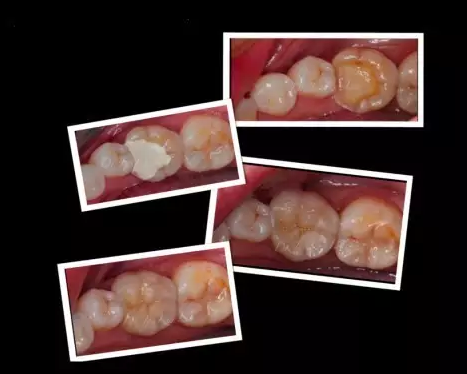

北京精德口腔補牙

這些嵌體,在終戴如患者口內的時候,真是的的。在使用上沒有任何的影響和不適,而且堅固耐用。做嵌體修復的時候,好的材質也對嵌體的修復果產生影響。

“嵌體,顧名思義就是是一種嵌入牙體內部的修復方法,是為牙齒量身定做的修復體,通過黏合劑將其黏在有缺損的牙齒上?!毙旅苄“淄醚揽棋X俊霞醫(yī)生稱,由于嵌體在形態(tài)、硬度等各方面與牙齒吻合度很好,所以,它不僅解決了牙齒缺失部分容易變大的難題,也減輕了患者頻繁補牙的痛苦。

7、嵌體的另一個優(yōu)點是,因為它的整個制作過程是在口外完成的,所以它還可以很好的恢復原來牙齒的外形,恢復原來牙齒的咀嚼率。而這一點,是傳統(tǒng)補牙無論如何都無法比擬。